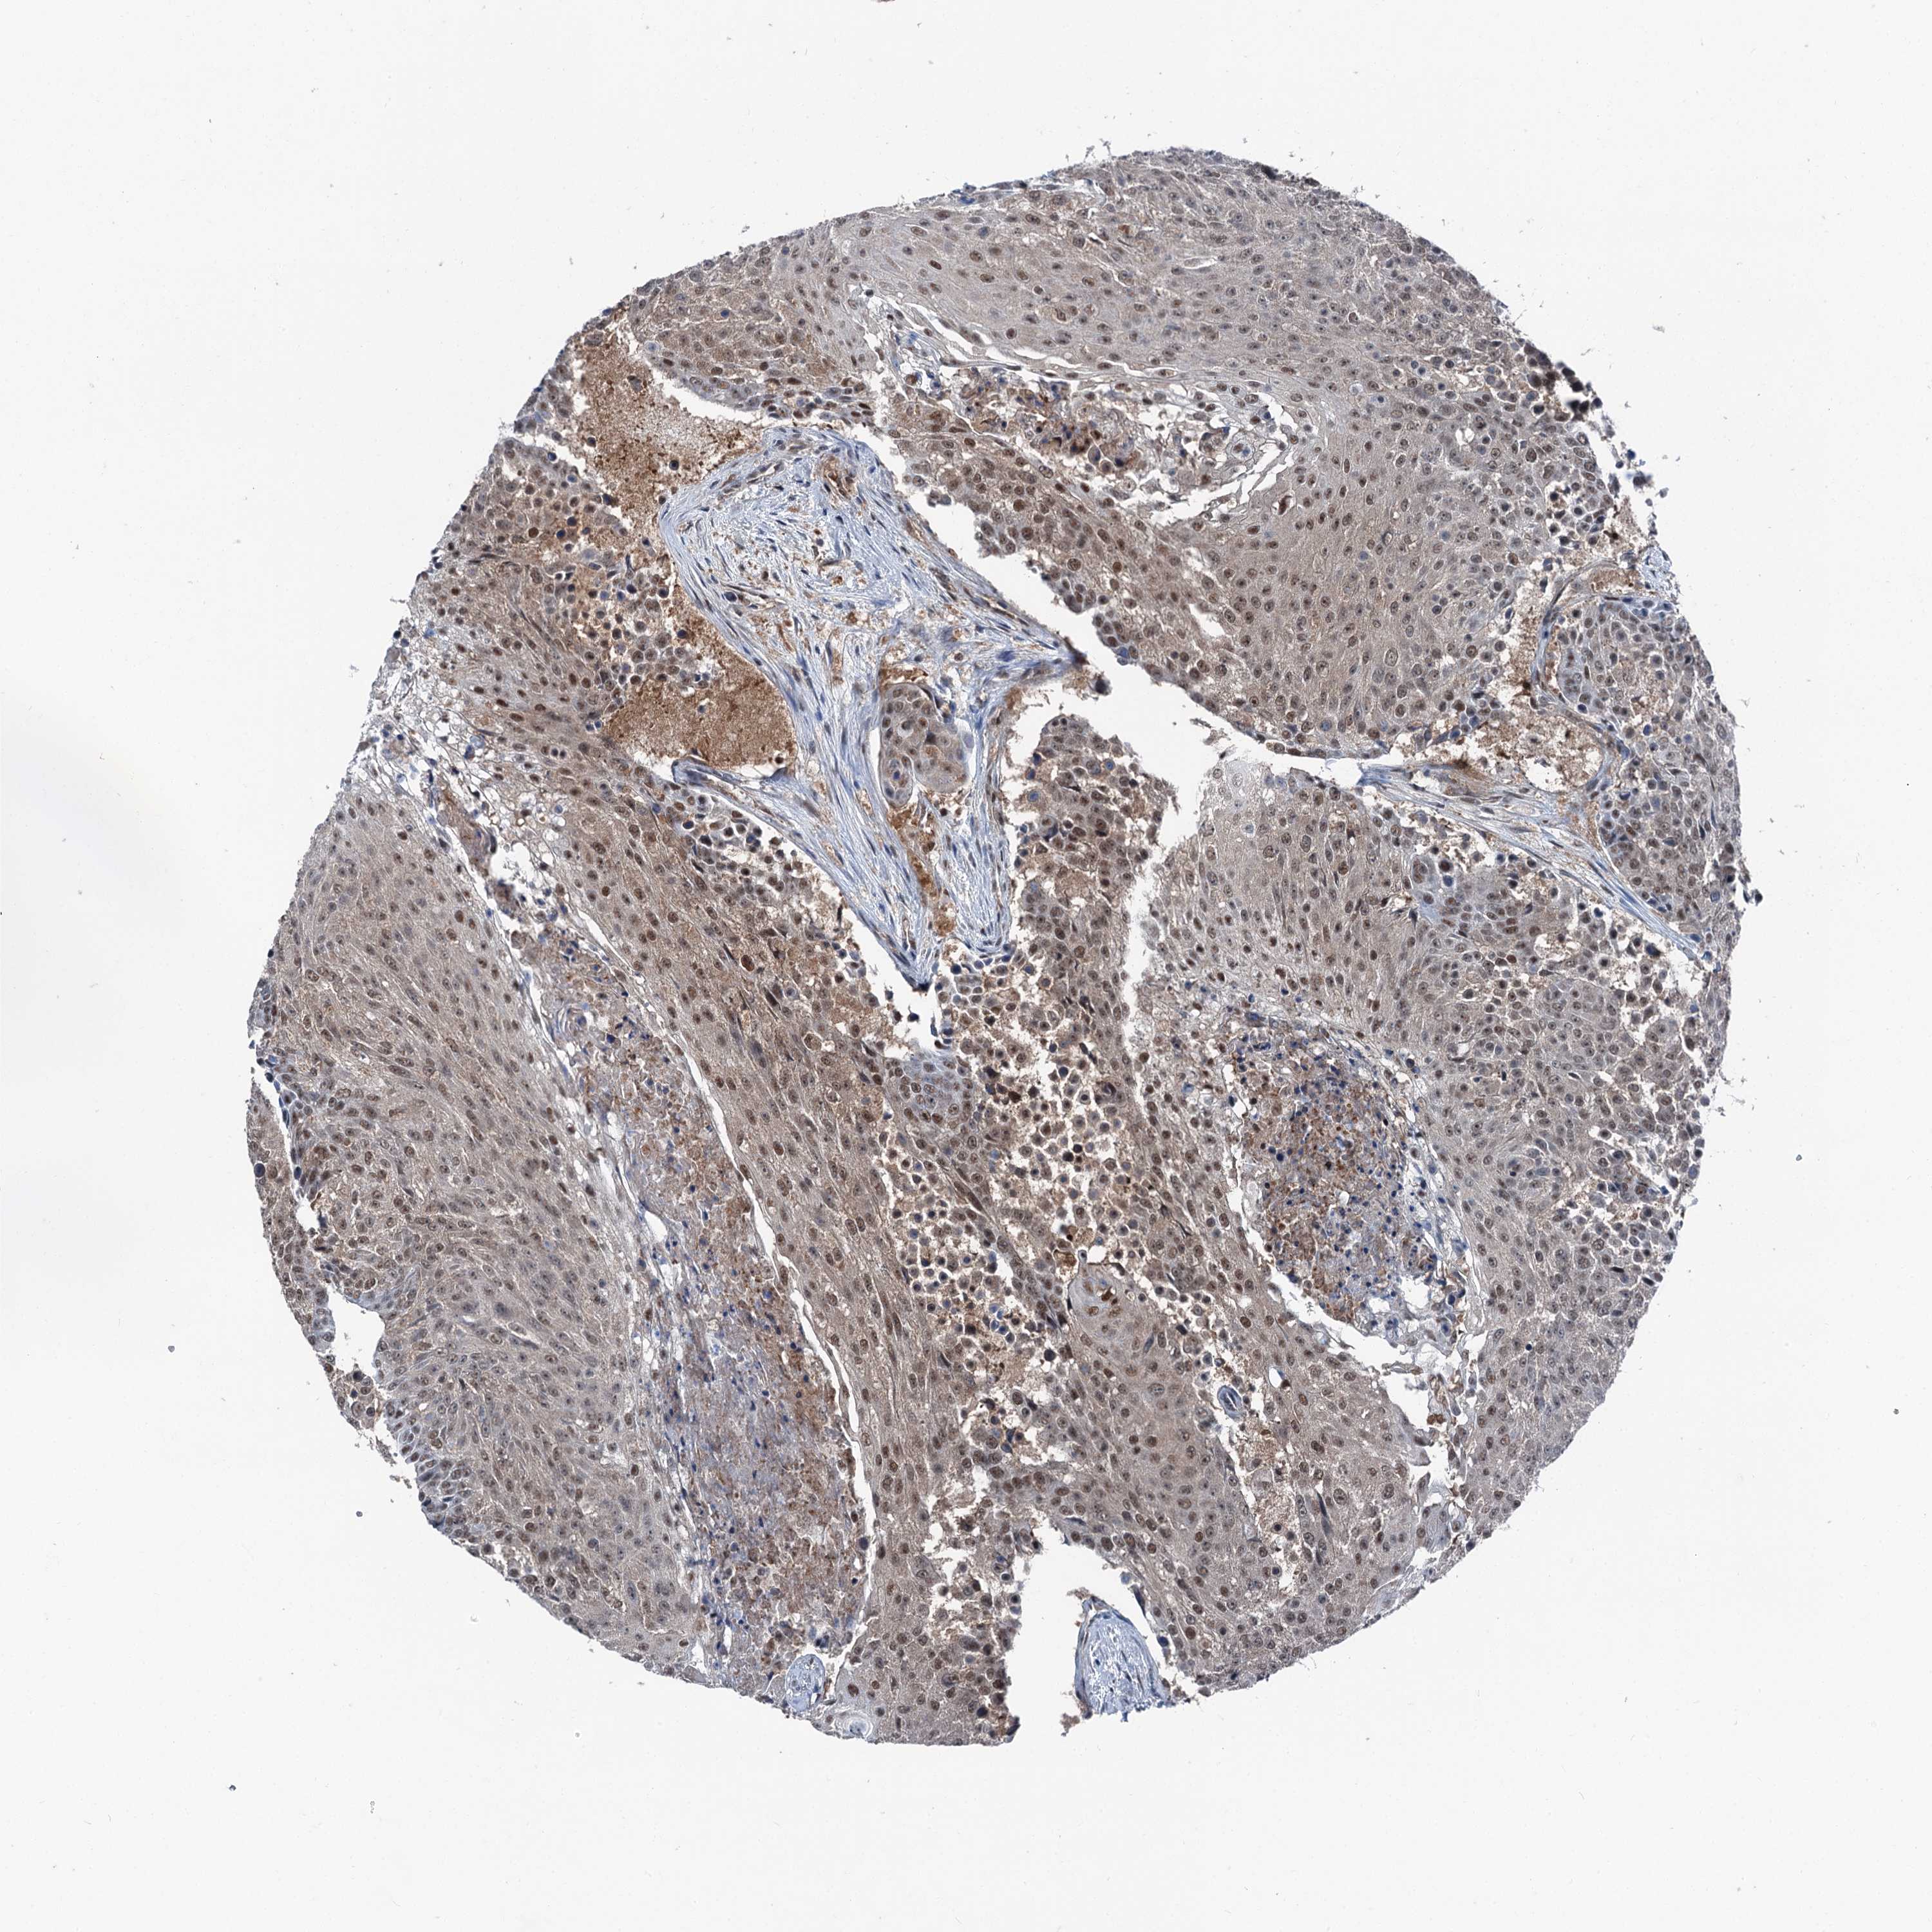

UROTHELIAL CANCER - Protein expressioni

A mouse-over function shows sample information and annotation data. Click on an image to view it in a full screen mode. Samples can be filtered based on level of antibody staining by selecting one or several of the following categories: high, medium, low and not detected. The assay and annotation is described here.

Note that samples used for immunohistochemistry by the Human Protein Atlas do not correspond to samples in the TCGA dataset.

Antibody stainingi

Antibody staining in the annotated cell types in the current human tissue is reported as not detected, low, medium, or high, based on conventional immunohistochemistry profiling in selected tissues. This score is based on the combination of the staining intensity and fraction of stained cells.

Each image is clickable and will lead to virtual microscopy that enables deeper exploration of all samples and also displays staining intensity scores, fraction scores and subcellular localization as well as patient and tissue information for each sample.

Antibody HPA038691

Antibody HPA038692

Staining

High

Medium

Low

Not detected

Intensity

Strong

Moderate

Weak

Negative

Quantity

>75%

75%-25%

<25%

None

Location

Nuclear

Cytoplasmic/membranous

Cytoplasmic/membranous,nuclear

Urothelial carcinoma, High grade